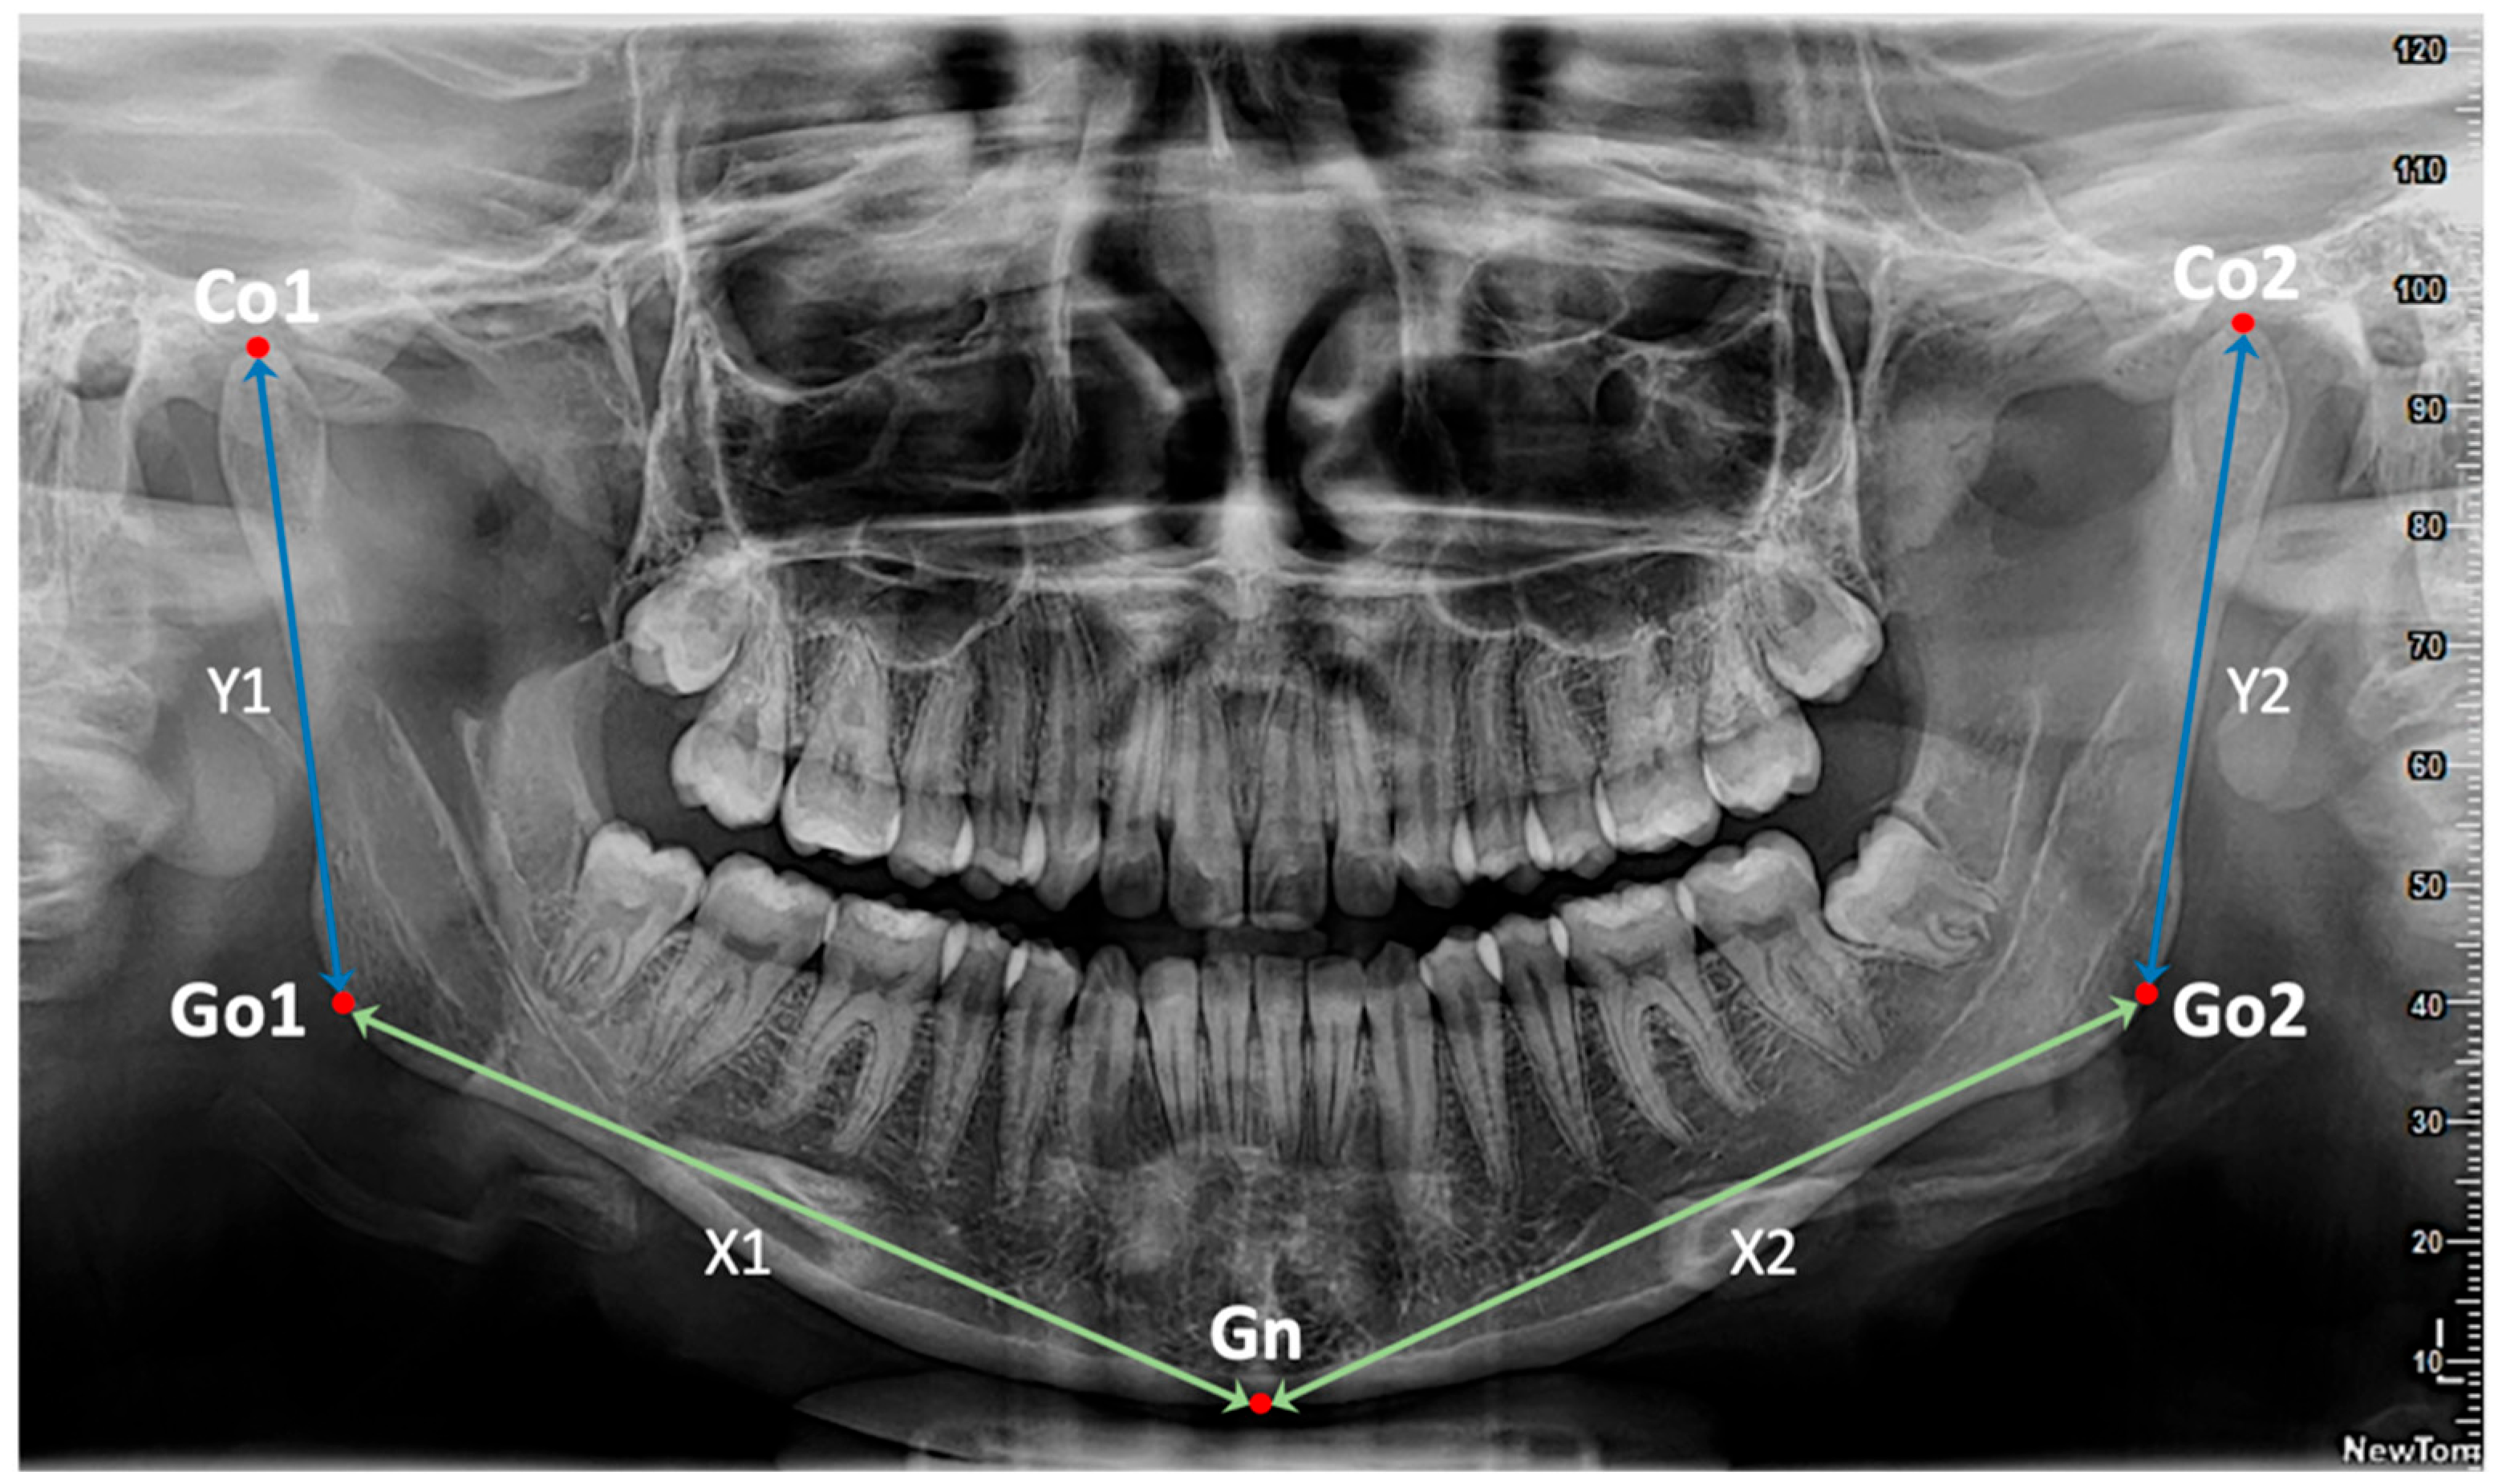

- Conversion and calculation of distances: the obtained coordinates were processed from the 5 anatomical landmarks (Co1, Go1, Gn, Go2, Co2) and representative linear measurements were extracted for the calculation of the 4 key Euclidean distances defined as, X1: distance between Go1 and Gn (right half of the mandibular body); X2: distance between Gn and Go2 (left half of the mandibular body); Y1: distance between Co1 and Go1 (right mandibular ramus); Y2: distance between Go2 and Co2 (left mandibular ramus). All obtained distances were converted from pixels to millimeters using a conversion factor specific to the analyzed images (0.10585 mm/pixel) (Figure 1).